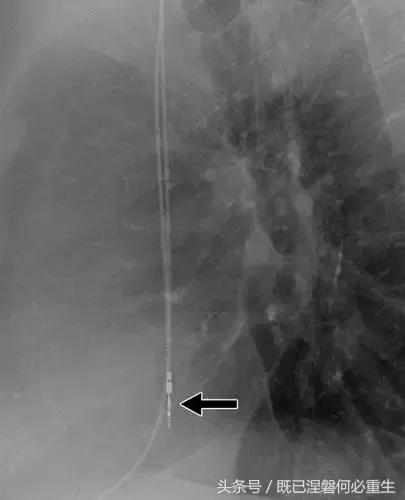

图。 7A 79岁的男性患有电极折断和迁移。

A,初始胸前X线片显示Pacesetter双腔起搏器低于锁骨的心房导线不完全断裂(变薄)(箭头)。

图。 7B 79岁的男性患有电极折断和迁移。

B,大约3年后,电极完全断裂,金属传导碎片(箭头)分离。 远端片段(箭头)已经偏移尾侧,但是由于围绕电极的射线可穿透鞘的约束效应而没有迁移到肺循环中。 引线和中心静脉导管最常见于锁骨和第一肋骨之间断裂,因为它们在臂运动期间被锁骨下肌肉或腱或肋锁韧带压缩[16]。